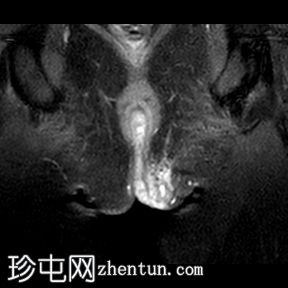

冠状位T2加权像

脂肪抑制像

一条低T1信号、高T2/PD信号的弧形瘘管连接肛门黏膜和左侧会阴皮肤,并伴有明显的管状强化。该瘘管从肛门黏膜后方6点钟方向穿过肛门内括约肌,然后穿过括约肌间隙,但未穿过肛门外括约肌。皮下少量积液提示脓肿形成。上述影像学表现符合2级括约肌间肛周瘘。

根据圣詹姆斯大学医院的分类,这是一例活动性 2 级括约肌间肛周瘘 1 型病例。